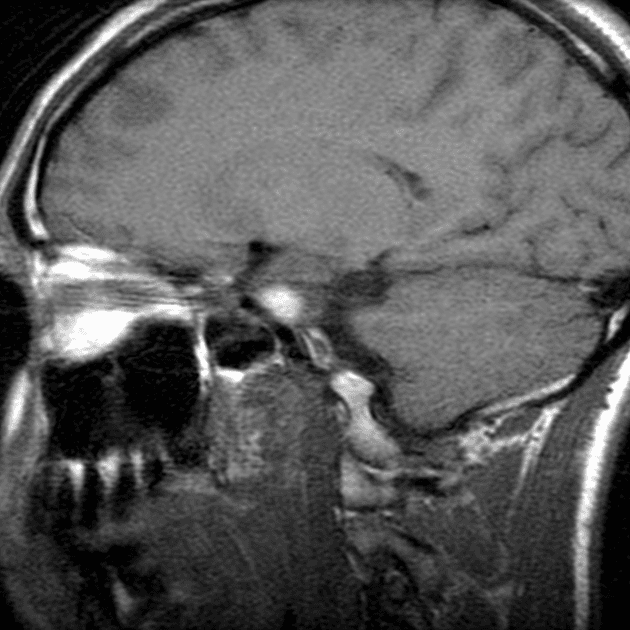

Sagittal T1

MRI•Sagittal T1•1 Img

- Khối liên tục với cuống yên, làm giãn cuống này cả phía trên và phía dưới.

- Phù hợp với kiểu tăng quang đặc trưng và nằm trong cuống yên (infundibulum).

- Khối phù hợp với kiểu tăng quang đặc trưng và nằm trong cuống yên (infundibulum).

- Khối liên tục với cuống yên, làm giãn cuống cả phía trên và phía dưới.

- "Đặc điểm hình ảnh gồm khối u ranh giới rõ, tăng quang mạnh, liên tục với và làm giãn cuống yên."

U Pituicytoma là một loại khối u thần kinh đệm lành tính, phát triển chậm và hiếm gặp, xuất phát từ các tế bào pituicyte ở thùy sau tuyến yên hoặc cuống yên. Khối u thường biểu hiện như một tổn thương ranh giới rõ, tăng quang mạnh và liên tục với, đồng thời làm giãn cuống yên. Trên cộng hưởng từ (MRI), khối u thường có tín hiệu đẳng trên hình ảnh T1 và tăng quang đồng nhất sau khi tiêm thuốc cản quang. Việc không có dấu hiệu ác tính, không bệnh toàn thân và tổn thương ổn định dài hạn trên hình ảnh học làm tăng khả năng chẩn đoán u Pituicytoma, ngay cả khi chưa xác định bằng mô bệnh học. Các chẩn đoán phân biệt bao gồm u tuyến yên có liên quan đến cuống yên, u màng não và bệnh tổ chức bào Langerhans, những bệnh này có thể có hình ảnh tương tự. Tuy nhiên, vị trí đặc hiệu trong cuống yên và sự liên tục với cuống làm nghiêng về chẩn đoán u Pituicytoma. Điều trị thường mang tính theo dõi bảo tồn, đặc biệt ở bệnh nhân không có triệu chứng.